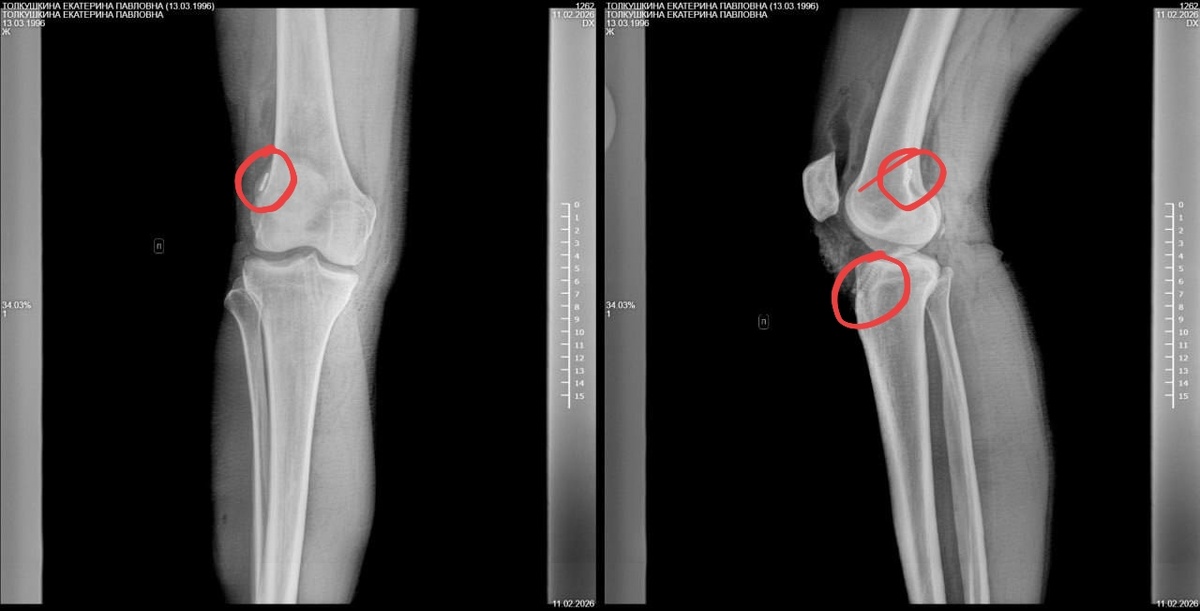

Вчера ещё сходила в туалет один раз, очень проблематично прыгать на одной трясущейся ноге и костылях. Но пока это мой максимум. Сегодня ещё два раза вставала: туалет и рентген (пересаживалась с кровати на кресло каталку). После каждого подъёма нога ноет пуще прежнего.

Винтик и пуговка